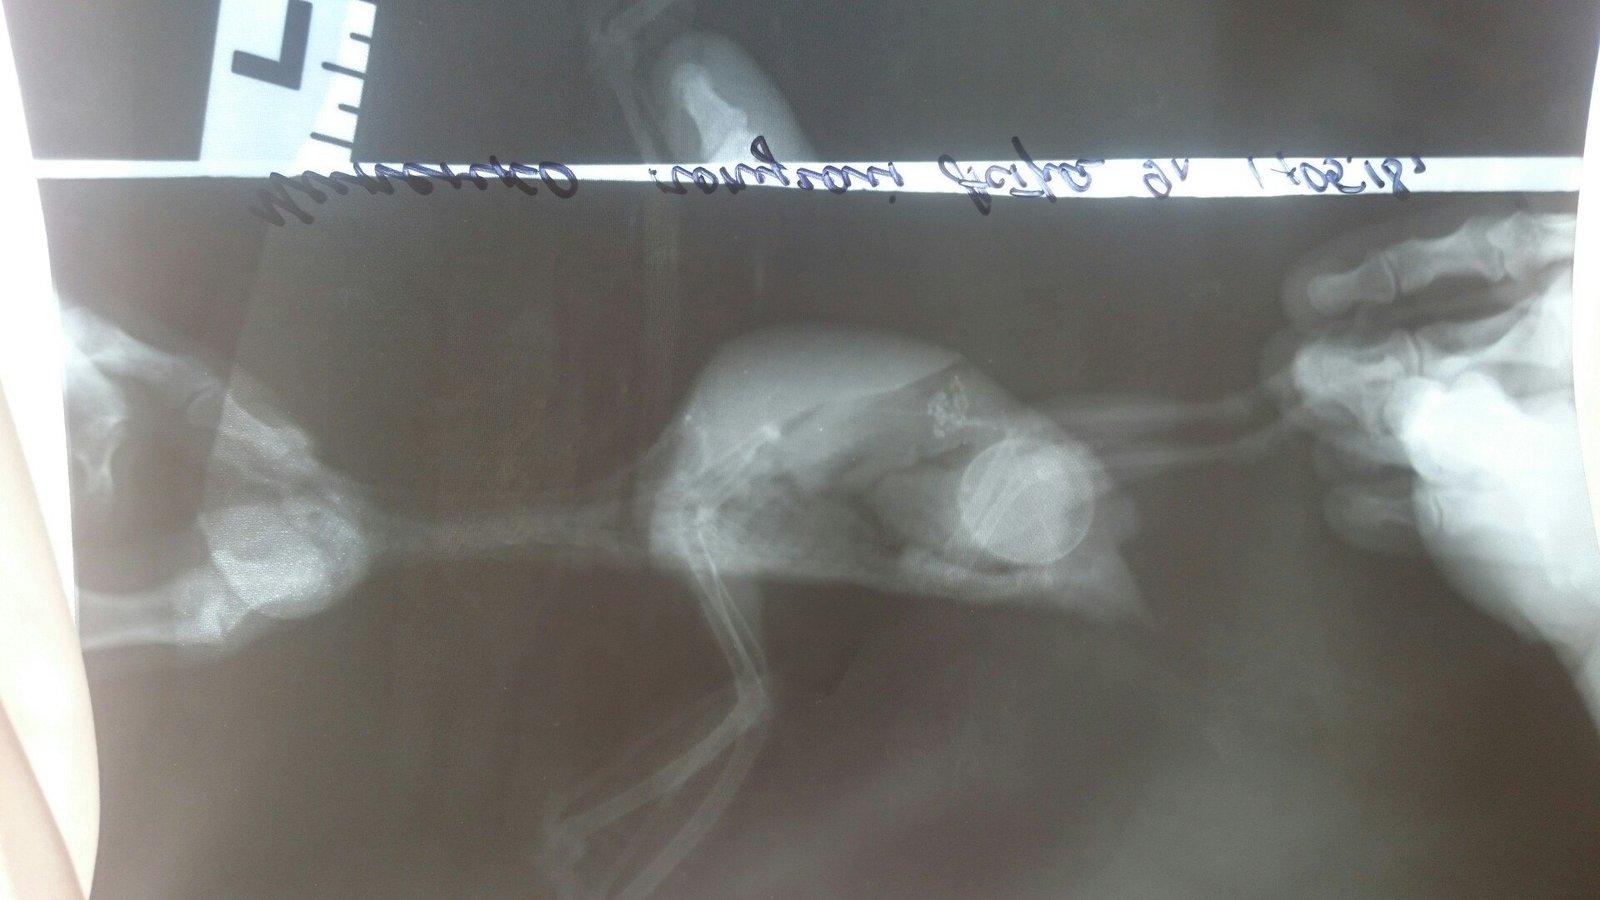

Вчера ездили в Симферополь, нам сделали рентген и анализы , сказали, что восполение клоаки, возможно храническое, и по почкам тоже что-то не очень в порядке, но анализ крови у таких мал. птичек не берут, прописали лечение) На подходе видно 3 яйцо, к-рое вчера было благополучно снесно на двери:bird:Надеюсь, лечение поможет

хорошо сделанная копра. Только йодофильной флоры не указано.

Терапия в принципе адекватная- и курс, и дозы.

Но не хватает нистатина(а он нужен- и как прикрытие энрофлоксацина, и отдельно- вон кандида есть в анализе).

Доза а птицу вашу- 50 000 ед в сутки, весь курс приема байтрила.

Далее обсудите с вашим врачом возможность введения гормонов- преднизолон+марвелон хотя бы.